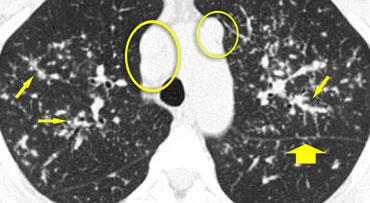

Hình ảnh

Bệnh nhân khác với Ung thư hạch bạch huyết lan tỏa có dày vách liên tiểu thùy (mũi tên vàng).

Kèm theo tràn dịch màng phổi (mũi tên xanh) và tổn thương di căn phổi (vòng tròn).